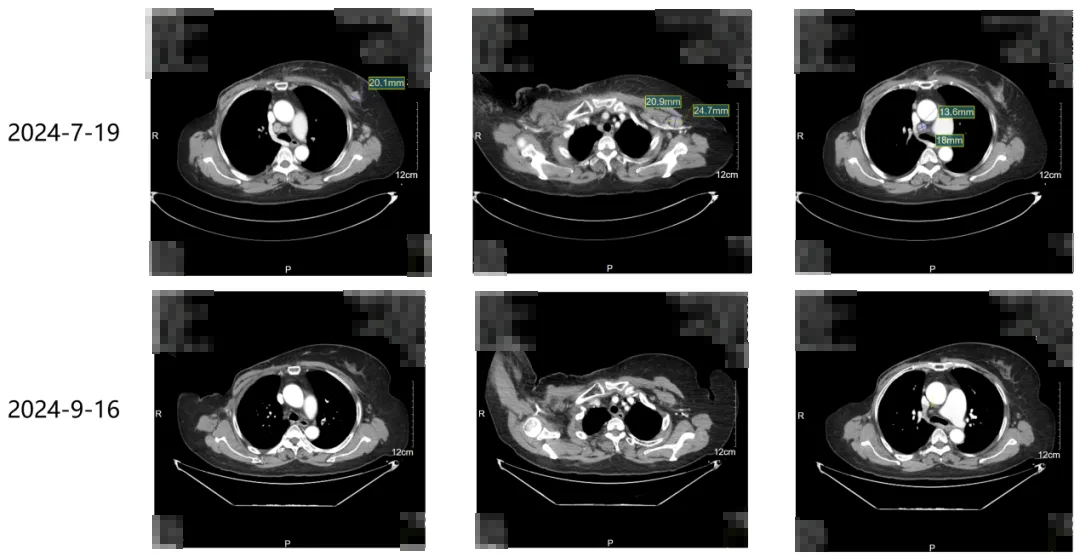

一线治疗:艾立布林+伊尼妥单抗+吡咯替尼3次,疗效PR。

·2024年9月16日本院随访